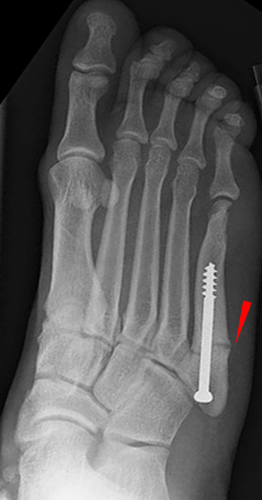

• It can also be confused with an avulsion fracture of the styloid due to contraction of the peroneus brevis muscle, usually occurring closer to the metatarsal styloid.

• The image on the left below shows a Jones fracture that was fixed with a screw to aid healing. The image on the right is an avulsion fracture.